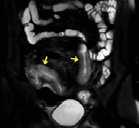

Souhrn: Úvod: Zobrazovací metody mají v diagnostice pacientů s Crohnovou chorobou nezastupitelnou úlohu. V současné době existuje několik skórovacích systémů, jejichž cílem je pomocí předem stanovených parametrů objektivizovat hodnocení zánětlivého postižení střeva. Cílem této práce bylo srovnání nálezu zánětlivého střevního postižení na koloskopii a magnetické rezonanci (MR) při použití skórovacího systému MaRIA. Materiály a metody: Pacienti s Crohnovou chorobou podstoupili v rozmezí do 2 měsíců koloskopii a MR enterografii ve Fakultní nemocnici Brno v letech 2020–2022. Aktivita onemocnění na koloskopii byla hodnocena pomocí SES-CD a Rutgeerts score, na MR pomocí MaRIA skóre (zesílení stěny, její sycení, edém a přítomnost ulcerací). Nálezy z obou zobrazovacích metod byly srovnány, koloskopie byla zvolena zlatým standardem. U každého pacienta bylo analyzováno terminální ileum, tlusté střevo (rozdělené anatomicky na čtyři segmenty) a rektum. Výsledky: V této retrospektivní studii bylo analyzováno 203 střevních segmentů u 43 po sobě jdoucích pacientů (42 % mužů). Senzitivita MR enterografie v hodnocení aktivity střevního zánětu byla 62 %, specificita 94 %. Všechny parametry určující aktivitu zánětu na MR byly signifikantně vyšší u pacientů s aktivitou dle koloskopie a celková hodnota MaRIA skóre byla rovněž vyšší v této skupině (12,76 ± 7,48 vs. 5,27 ± 3,45; p < 0,001). Senzitivita se zvýšila na 90 % při izolované analýze tenkého střeva, při analýze tlustého střeva se naopak snížila na 34 %. Závěr: V naší studii jsme prokázali shodu mezi MR s použitím MaRIA skórovacího systému a koloskopií při hodnocení střevního zánětu u pacientů s Crohnovou chorobou. Klí ová slova: magnetická rezonance – koloskopie – Crohnova choroba – MaRIA